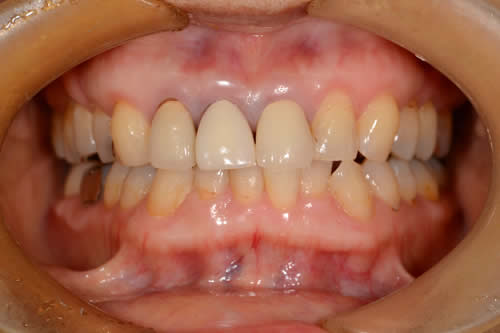

主訴:前歯ぐらつく

治療内容

上の前歯2本を抜歯し、インプラントを行い

セラミックを装着

| 治療期間 | 1年 |

| 治療費 | 約800,000円 + 税 |

| 治療のリスク | インプラントも歯周病になる可能性がある |